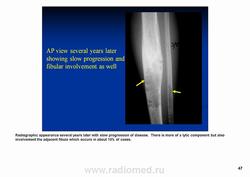

Классический радиологический облик

Но возникает вопрос.

А "это" похоже на "классический радиологический облик" адамантиномы, или нет?